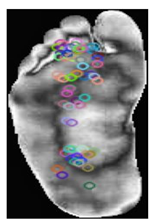

The smaller the Hamming distance, the more similar the two descriptors are, and the more likely the key points are to match. This computationally efficient process is crucial for real-time applications, such as object recognition. The compact descriptor size of N × 32 ensures memory efficiency, making ORB particularly suitable for real-time applications such as object recognition. As shown in Table 3, samples of the normal and DFUs keypoints were extracted.

Table 3.

Samples of normal and DFUs key points.